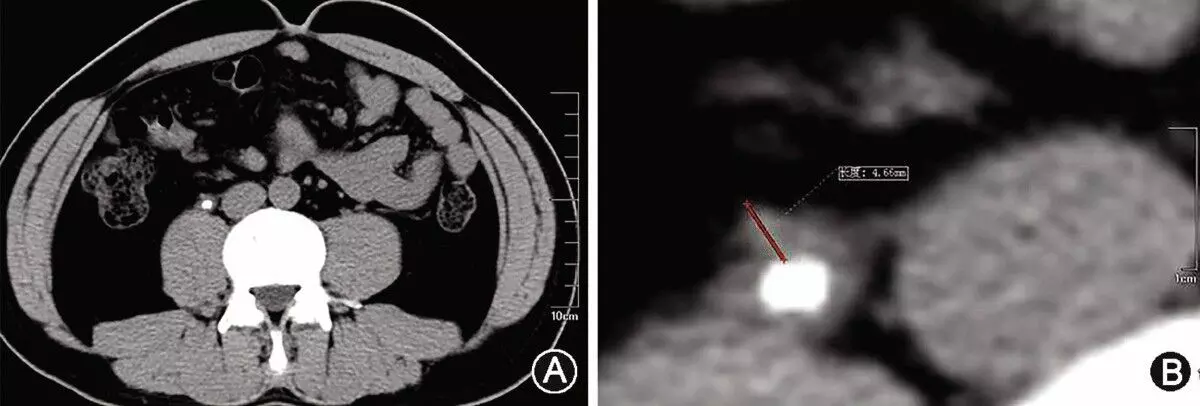

This multicenter, randomized trial focused on patients who experienced an acute intracerebral hemorrhage, specifically the individuals with lobar or anterior basal ganglia hemorrhages and had hematoma volumes between 30 to 80 milliliters. The participants were divided into a group receiving minimally invasive surgical removal of the hematoma along with standard medical treatment and another the other group receiving only medical management according to the existing guidelines.

The primary goal of this study was to evaluate the effectiveness of surgical intervention in improving the patient outcomes which was measured by the utility-weighted modified Rankin scale. This scale ranges from 0 to 1, where the higher scores signify better functional outcomes according to the patient assessments. A total of 300 patients were enrolled, with the trial noticing an adaptation part-way through after 175 patients had joined where this shift limited further enrollments to only the individuals with lobar hemorrhages due to an observed trend in the data.

The results from the study indicated a notable difference in recovery outcomes. The surgery group had an average score of 0.458 on the modified Rankin scale when compared to 0.374 in the control group 6 months after treatment. This difference was statistically significant and suggested a clear benefit of surgical intervention among the patients with lobar hemorrhages. In this subgroup, the mean score difference was more pronounced at 0.127 in favor of surgery. However, for the individuals with anterior basal ganglia hemorrhages, surgery did not show a notable benefit.

Only 9.3% of patients in the surgery group died within 30 days of enrollment, when compared to 18.0% in the control group which points to the reduction in early mortality rates. This significant decrease illuminates the additional benefit of surgical intervention in managing acute intracerebral hemorrhages. However, the surgical approach evidenced a 3.3% incidence of postoperative complications like rebleeding and neurological deterioration in the surgery group. Overall, these findings suggest that for certain patients with specific types of brain hemorrhages, early minimally invasive surgery could be a beneficial treatment option that offers improved functional outcomes and lower mortality rates.